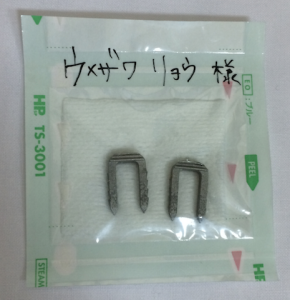

上の写真は移植した膝屈筋腱を固定しているボルトを日立メディコ社のエコー機器「HI VISION Preirus」で確認している様子です。ボルトの感覚は最近ではほとんど気にならなくなりましたが、今年の8月以降、ボルトを外す手術が再度必要になるので、それまでに筋力トレーニングを頑張ろうと思います!